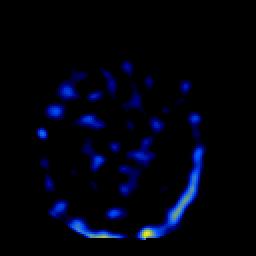

SPECT TL Study #2 -- Slice #25

[Home][Help][Clinical][Tour 1][Tour 2][Tour 3] Slice 25